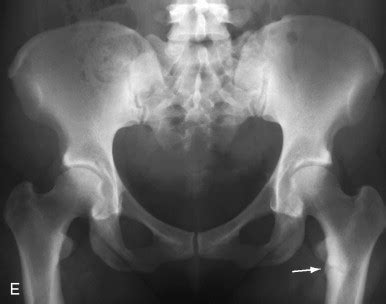

Alright folks, let’s get down to the nitty-gritty of what we actually see on those X-rays when we suspect osteomalacia . The star of the show, the one finding that most people associate with osteomalacia, is undoubtedly the Looser zone . These guys are also known as pseudofractures or Milkman’s lines, and they are absolutely key. Imagine a thin, horizontal lucent line crossing the bone, usually perpendicular to the cortex. They’re not true fractures in the sense of a complete break, but rather areas of incomplete healing or unmineralized osteoid. The most common locations for Looser zones are the inner aspect of the femoral neck, the pubic rami, the ribs, the scapulae, and the shafts of long bones. When you see these, especially multiple ones, it’s a pretty strong indicator that something is up with bone mineralization. It’s like finding a series of tiny, horizontal cracks in a piece of pottery. Remember, these are not through-and-through fractures; they are often quite subtle and can be easily missed if you’re not specifically looking for them. The bone on either side of the Looser zone might appear sclerotic (denser), which can make the lucent line stand out more. Another significant radiographic finding is generalized osteopenia . This means the bones, overall, appear less dense than they should be. On an X-ray, this translates to the bones looking more gray and less white. The trabecular pattern within the bone might also become less distinct and more coarsened, losing its fine, intricate mesh-like appearance. Think of it like the intricate lace of a healthy bone becoming a more blurry, chunky pattern. We also need to be vigilant for fractures . In osteomalacia, patients are prone to insufficiency fractures , which are fractures that occur with minimal or no trauma due to the weakened state of the bone. These can occur in various locations, including the spine (vertebral compression fractures), pelvis, and long bones. These fractures might not always have the typical sharp, clean edges of acute fractures; they can sometimes appear more ill-defined or sclerotic. The cortical bone , the smooth outer shell of the bone, can also be affected. It might appear thinned and indistinct, with loss of its sharp, clear outline. In some cases, the ends of the long bones might appear widened or flared due to the accumulation of unmineralized osteoid. The overall appearance of the bone can sometimes be described as “mottled” or “chalky” . It’s crucial to differentiate these findings from other conditions that can cause osteopenia or fractures, such as osteoporosis, hyperparathyroidism, or metastatic disease. This is where our knowledge of typical distributions and appearances comes into play. By carefully analyzing these classic radiographic findings – Looser zones, osteopenia, fractures, and changes in cortical and trabecular bone – we can confidently diagnose osteomalacia radiology and guide the appropriate management for our patients.

When it comes to osteomalacia radiology , our main job is to be the first line of defense, spotting those subtle (and sometimes not-so-subtle) signs that point towards this bone-weakening condition. It’s all about using our imaging tools effectively to catch what might otherwise be missed. X-rays are typically the go-to initial imaging modality. They’re readily available, cost-effective, and can often reveal the classic radiographic findings of osteomalacia. However, it’s super important to remember that plain X-rays might appear normal, especially in the early stages of the disease. So, don’t get discouraged if the first set of images doesn’t scream “osteomalacia!” We need to be patient and know what we’re looking for. When the disease is more advanced, however, we start seeing those characteristic changes. One of the most hallmark signs we look for are Looser zones , also known as pseudofractures. These appear as relatively wide, short, transverse radiolucent lines that are typically found in areas of stress, like the proximal femur, pelvis, ribs, and scapulae. They represent areas where the bone has failed to mineralize and essentially has microscopic fractures that haven’t healed. They’re a dead giveaway, guys! It’s like finding a crack in a building’s foundation – you know something’s seriously wrong. Another important finding is diffuse osteopenia , which is a generalized decrease in bone density. The bones just look less white and more gray on the X-ray, indicating less mineral content. Think of it as the bone becoming more transparent. We also look for fractures , especially insufficiency fractures, which occur with minimal or no trauma. These can be anywhere but are common in the long bones and spine. The bones might also appear mottled or have a coarse trabecular pattern , losing that fine, intricate network we usually see in healthy bone. Sometimes, the cortical bone – the dense outer layer of the bone – can appear thin and indistinct. Beyond plain radiographs, other imaging modalities can be helpful. CT scans can provide more detailed cross-sectional views and are particularly good at visualizing Looser zones and subtle fractures that might be missed on X-ray. MRI is less commonly used for the primary diagnosis of osteomalacia but can be useful in assessing associated muscle abnormalities or complications like stress fractures. The key takeaway here is that osteomalacia radiology isn’t just about spotting one specific sign; it’s about recognizing a constellation of findings that, when put together, paint a clear picture of impaired bone mineralization. Our role as radiologists is crucial in identifying these subtle changes, differentiating them from other bone conditions, and providing the referring physician with the information they need to manage the patient effectively.